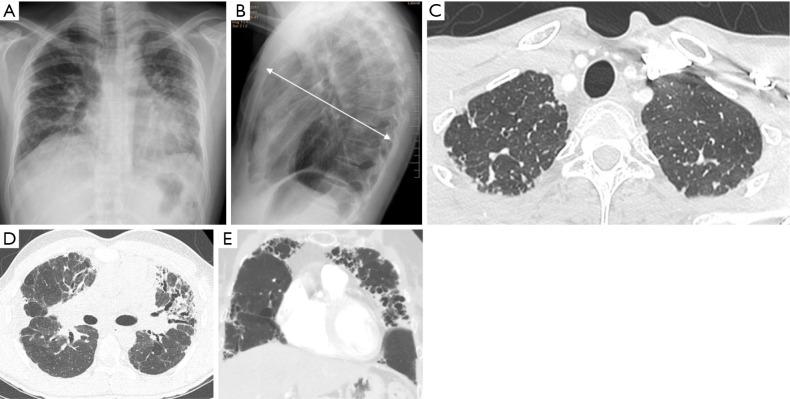

BACKGROUND AND OBJECTIVE

Interstitial lung diseases (ILDs) encompass over 200 entities. Among them, fibrosing lung diseases, have recently generated special interest due to the emerging therapies for their management. However, it is important to deepen our knowledge of other less prevalent ILD, since many of them are associated with a poor prognosis. This narrative review aims to provide a practical and up-to-date description of some poorly recognized ILD. It covers rare idiopathic interstitial pneumonias and their histologic patterns, genetic disorders with interstitial lung involvement (Hermansky-Pudlak syndrome), and ILD associated with benign proliferation of pulmonary lymphoid tissue, namely follicular bronchiolitis and granulomatous-lymphocytic interstitial lung disease.

KEY CONTENT AND FINDINGS

Despite the low prevalence of these diseases, the increased recognition of radiological patterns, pathological features, and diagnostic procedures, have permitted their better characterization. This review highlights epidemiology, clinical presentation, diagnosis, natural history, and treatment.